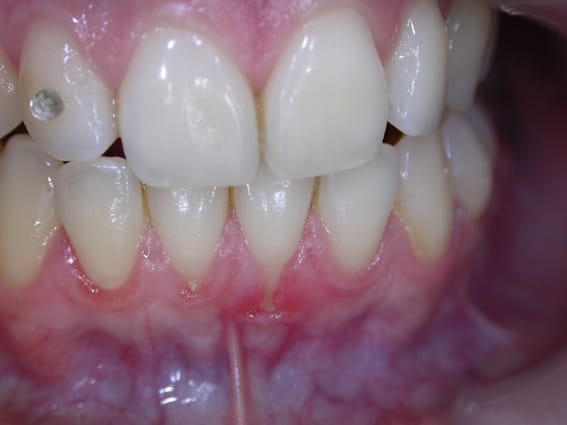

comme evoqué avec l'amibe....voila ce cas d'une jeune patiente sur qui j'ai fais une greffe conjonctive il y a 1 an et qui vient en contrôle .....le contrôle de plaque n'est parfait mais j'ai fait ouvrir et pris la photo comme ca .....

ce qui me pose question c'est que ce qui recouvre les racines en vestibulaire est dur .....y a t il de l'os et si oui quel type d'attache en dessous .....ankylose , os + EJL, os + attachement conjonctif ou Neoattache ?.....en tout cas l'amibe il n'y a pas de poche vestibulaire !!

je n'ai pas trouvé de doc sur ce type de constatations et c'est pas la première fois que je vois ce genre de resultat